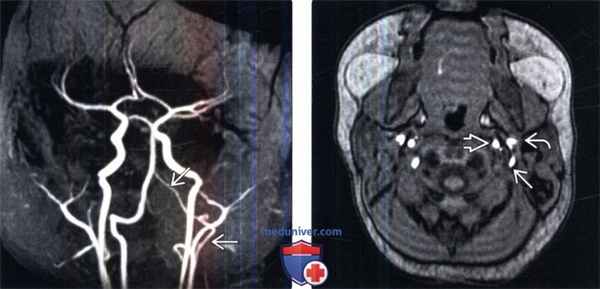

(Слева) На ангиограмме в боковой проекции контрастирована межсегментарная артерия проатланта 1 типа, берущая начало от ВСА и через большое затылочное отверстие анастомозирующая с базилярной артерией.

(Слева) На МР-ангиограмме в косой проекции видна межсегментарная артерия проатланта 2 типа, берущая начало от левой НСА и анастомозирующая с базилярной артерией.

(Справа) На исходной аксиальной МР-ангиограмме хорошо видно взаиморасположение левых НСА, ВСА и межсегментарной артерии проатланта 2 типа га на уровне шеи. Обратите внимание на отсутствие контрастирования нормальной левой позвоночной артерии в просвете отверстия поперечного отростка слева.